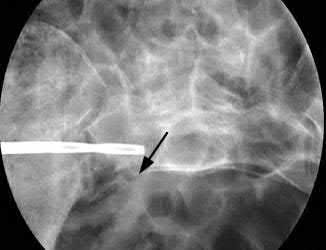

A 12-year-old obese boy presents with vague left thigh and knee pain. He is diagnosed with a Slipped Capital Femoral Epiphysis (SCFE) as seen in similar clinical scenarios. During percutaneous in-situ fixation, unrecognized penetration of the guide wire into the hip joint occurs. What is the most likely specific complication resulting from this technical error?

Chondrolysis is a severe complication of SCFE characterized by rapid destruction of the articular cartilage. While it can occur idiopathically, its most established iatrogenic cause is unrecognized intra-articular hardware penetration. The 'approach-withdraw' fluoroscopic technique is required during pinning to assure pins are entirely intraosseous. Avascular necrosis (AVN) is usually due to damage to the epiphyseal blood supply (retinacular vessels) secondary to the initial displacement, forceful closed reduction, or posterosuperior pin placement.